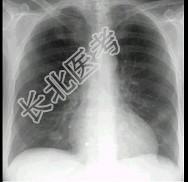

- 单项选择题多发性骨髓瘤患者出现咳嗽,咳痰, 气急,胸片检查发现病变后行CT检查如图, 最可能的诊断为 ( )

A、肺部感染

B、两肺结核

C、骨髓瘤转移肺部

D、肺淀粉样变性

E、肺转移瘤